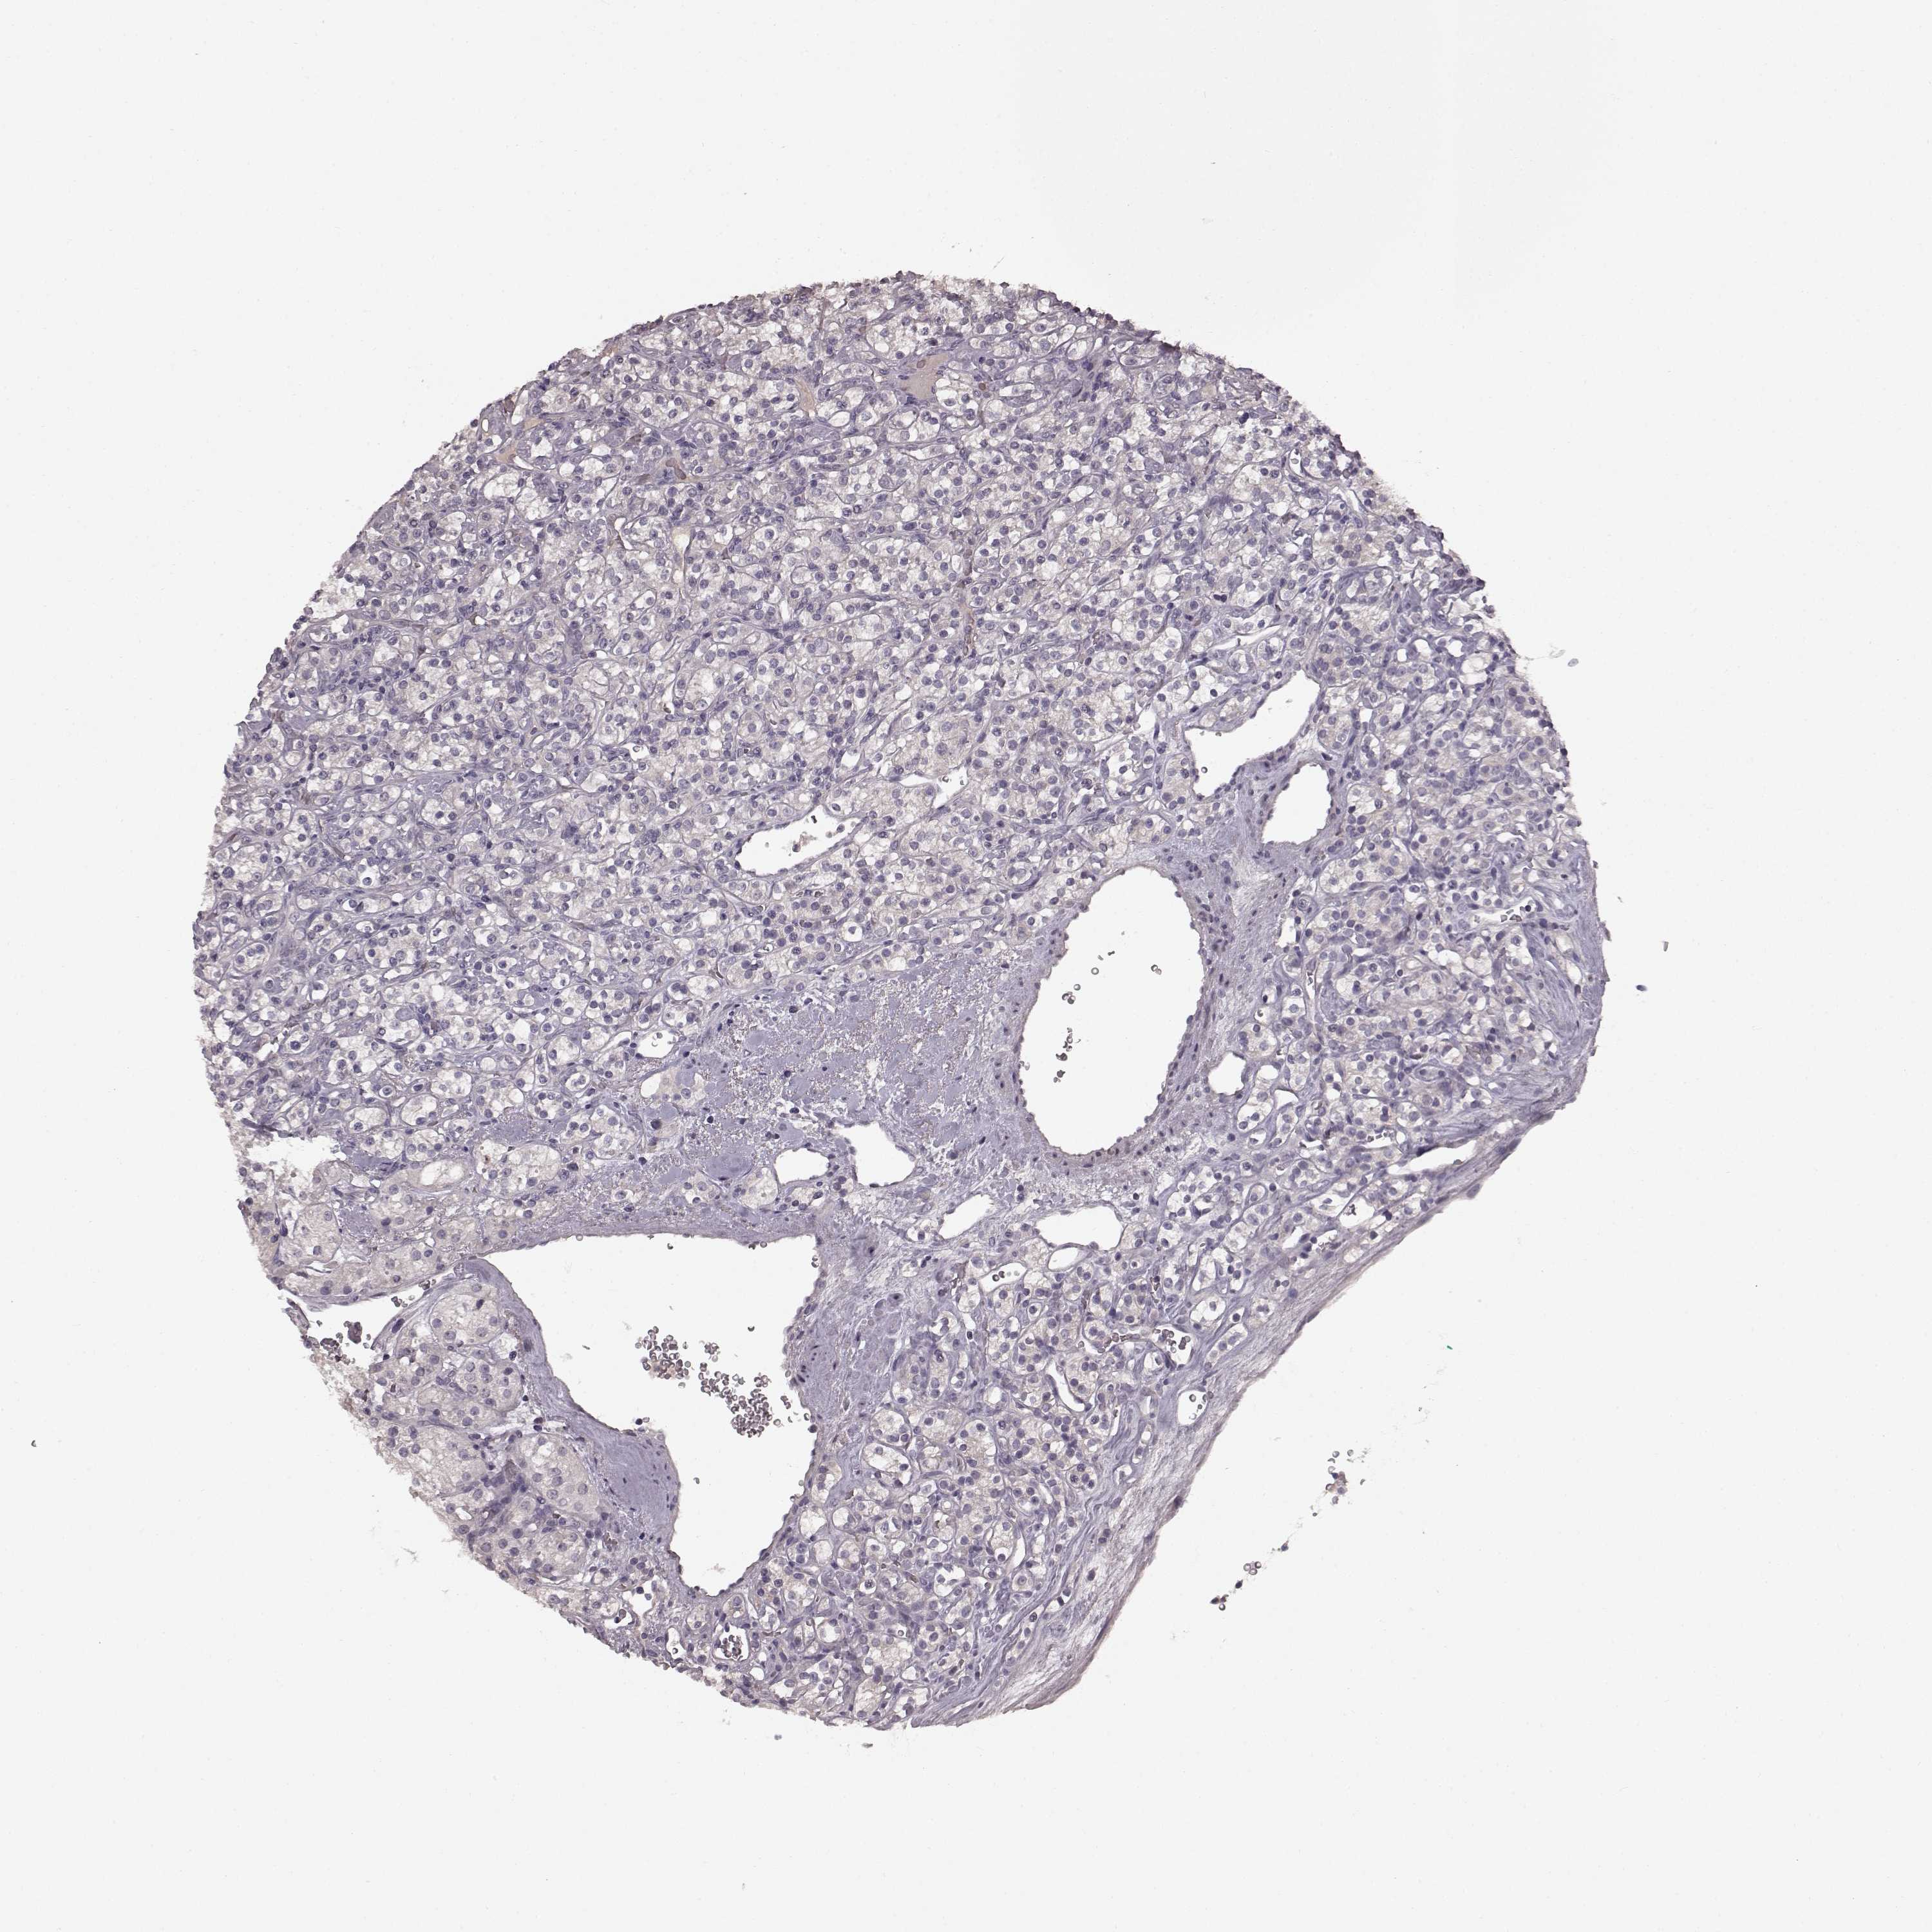

KICH TCGA KIRC TCGA KIRC VALIDATION KIRP TCGA PROTEIN RCC CPTAC PROTEIN EXPRESSION

Renal cancer

Kidney renal clear cell carcinoma

KIDNEY RENAL CLEAR CELL CARCINOMA (TCGA) - Interactive survival scatter ploti

SLC22A18 is not prognostic in Kidney Renal Clear Cell Carcinoma (TCGA)

Average pTPM 18.6

Number of samples 521